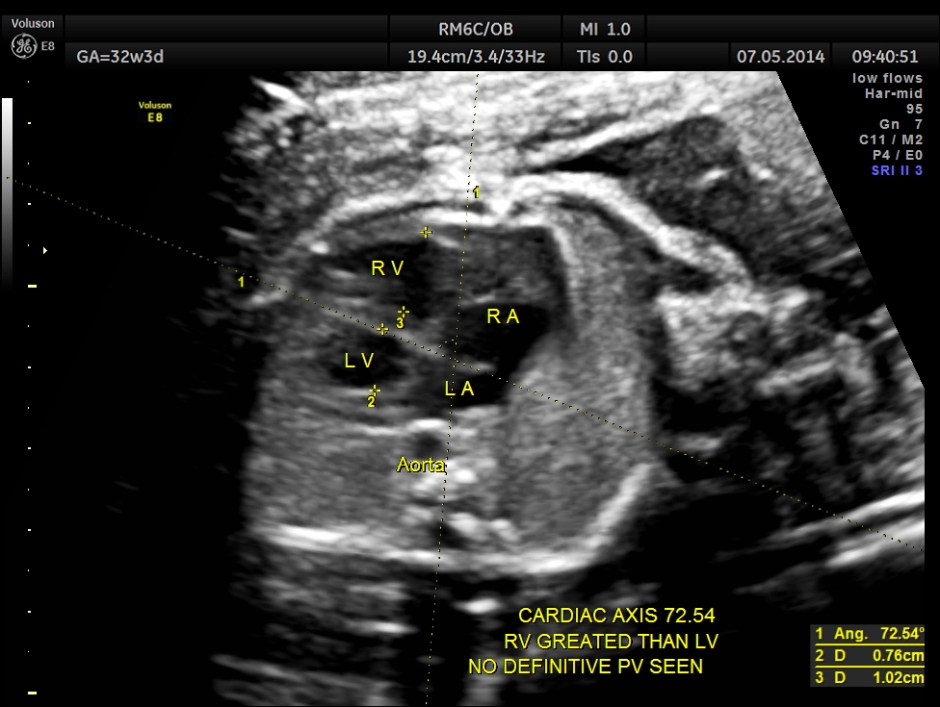

Cardiac axis is abnormal.

LA & LV appear to be smaller than RA & RV.

The situs appeared to be normal.

No definitive pulmonary vein draining into the left atrium could be made out . A common transverse vessel was seen beneath the left atrium . The LA & RA were smaller than the RA. Similarly the Aorta and the aortic arch were smaller than the pulmonary artery and the ductal arch due to the increased flow in the right side.

So a probable diagnosis of Total Anomalous Pulmonary Venous Connection with severe symmetric fetal growth restriction was offered. The patient apparently went into a spontaneous abortion and no autopsy study was done. So there is no confirmation again.